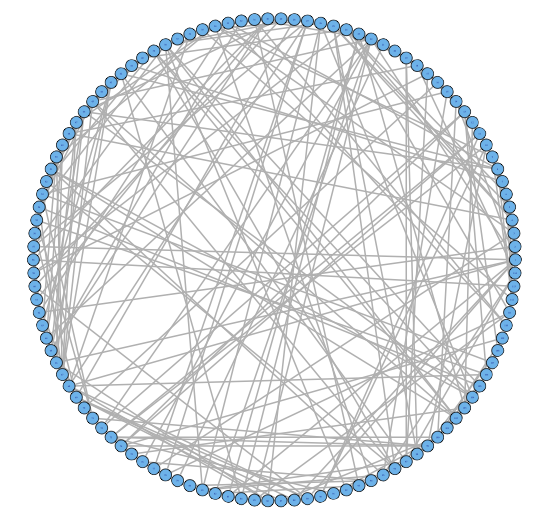

For our two-level problem (1.1.1), we must account for two sources of network variability when conducting population inference: (i) variability between subjects within a group and (ii) variability of the network selection procedure within a single subject. To see this, let us study a real multi-subject fMRI example. In Figure 2, we show estimated functional brain networks for subjects from the UCLA fMRI ABIDE data set INDI (2013). We describe the details of this data set, our pre-processing, and brain parcellation later in the Case Study in Section 5. In the top and middle panels, we estimate brain networks for each subject using graph selection methods for Gaussian graphical models (see Section 3.1 for details) and plot these as circle graphs to easily visualize network differences. It is clear that there are not only differences between autistic subjects and control subjects, but there is also large heterogeneity across subjects within each group. This is well-known in the neuroimaging literature (Milham et al., 2012; Nielsen et al., 2013), and makes finding statistically significant differences between subject groups much more challenging.

Less well studied in neuroimaging, is the second source of variability which arises from estimating networks for each subject instead of directly observing the networks. In the bottom panel of Figure 2, we re-estimate brain networks for a single control subject with bootstrap resampled data. It is clear that there is major intra-subject variability arising from our graph selection procedure. Indeed in neuroimaging, test–re-test studies which conduct brain imaging on the same subject in repeated sessions have shown high variability in the subject’s estimated brain networks (Wang et al., 2011). This also motivates the necessity of using a two-level model like (1.1.1) for population network inference as opposed to the one-level model and test statistics of the standard procedure.